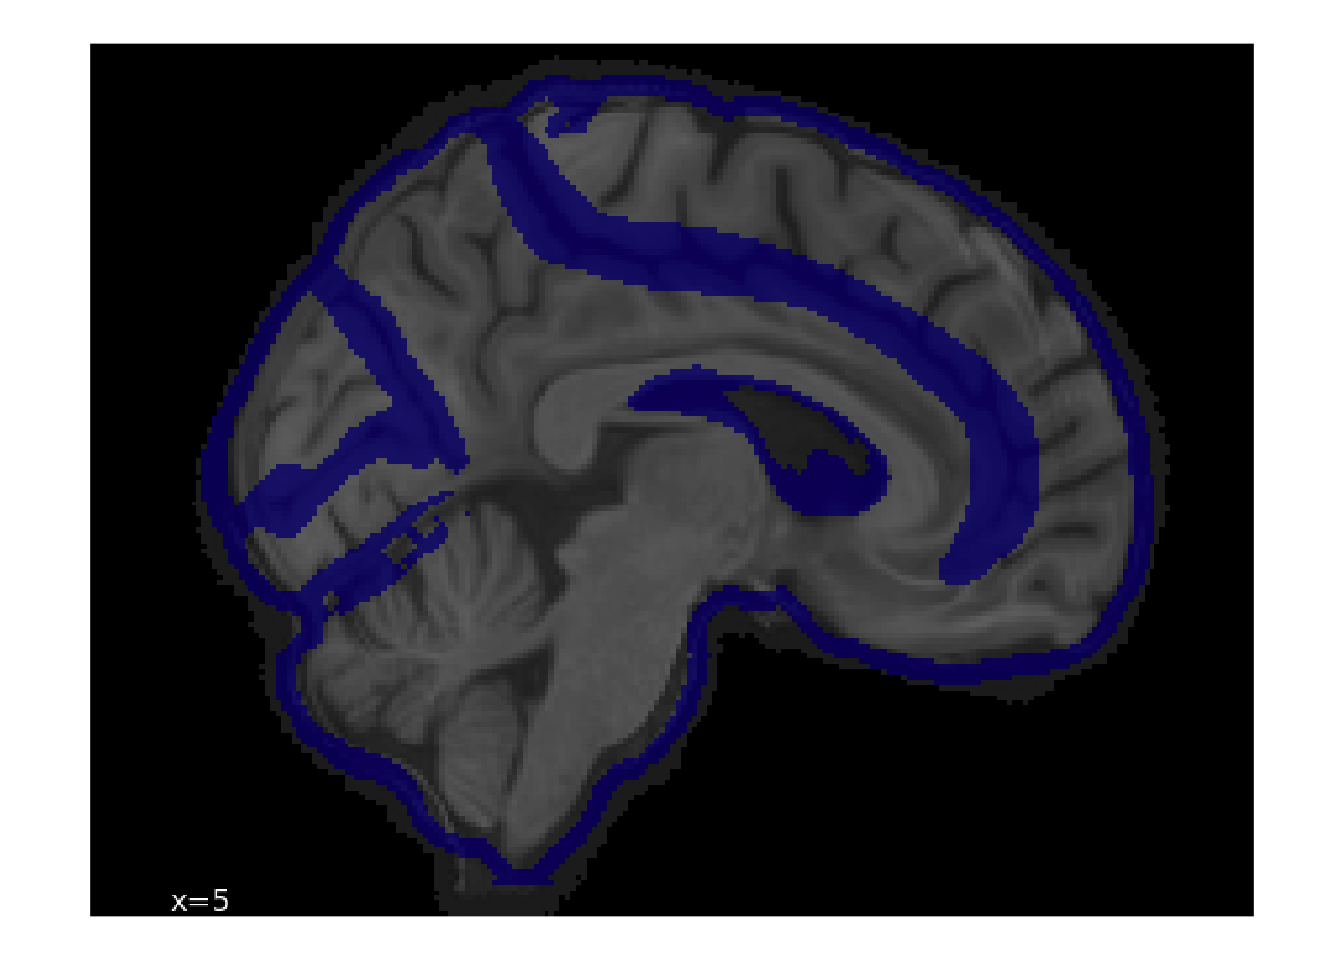

18.1.2 Example Image Plotting

Let’s see how we can display the rated images. As an example, we’ll look one of the spatial normalization images.

# grab images associated with spatial normalization

spatial_norm_images <- read_parquet_duckdb("data/qc/image.parquet") |>

filter(step == 1, display == 0) |>

select(id, img)

# grab image with lots of clicks

img_with_many_clicks <- read_parquet_duckdb("data/qc/coordinate.parquet") |>

filter(!is.na(x)) |>

semi_join(spatial_norm_images, by = join_by(img_id == id)) |>

summarize(n_clicks = n(), .by = c(img_id)) |>

slice_head(n = 1, by = n_clicks)

img_with_many_clicks| img_id | n_clicks |

|---|---|

| 15820 | 8 |

We’re going to need a helper function to convert the img BLOBs into a tibble for display with ggplot.

}Now, return to the image.parquet file, do a filter join to get just a single row, select it, apply the helper, and plot.

# now show the associated blob

read_parquet_duckdb("data/qc/image.parquet") |>

semi_join(img_with_many_clicks, by = join_by(id == img_id)) |>

pluck("img", 1) |>

readPNG() |>

to_tbl() |>

ggplot(aes(x = x, y = y)) +

geom_spatial_rgb(aes(r = r, g = g, b = b)) +

coord_fixed() +

theme_void()

By referring back to img.parquet file, we can see metadata about the source file.

select(-img)| id | slice | file1 | file2 | display | step | created |

|---|---|---|---|---|---|---|

| 15820 | 1 | sub-20045_ses-V1_space-MNI152NLin2009cAsym_desc-preproc_T1w.nii.gz | NA | 0 | 1 | 2025-07-28 13:44:04 |